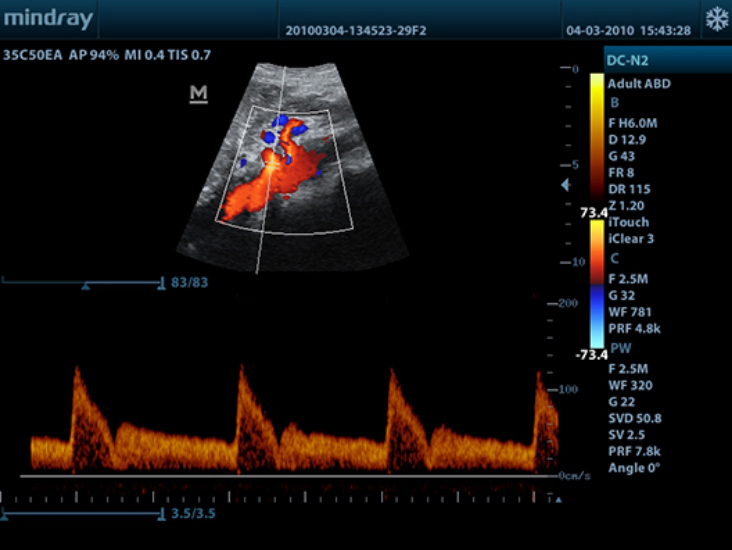

DC-N2

Color Doppler within Reach

DC-N2 offers a unique combination of relevant technology, quality and affordability. Be it an experienced ultrasound professional or a beginner, the DC-N2, with its unique self-learning software and advanced imaging technologies can be used across multiple clinical settings. With a user-friendly control panel and a user-centric workflow system, the DC-N2 can be well trusted for its performance and ease of use.

Multiple Beam Formation

Maximum 4 times tasking for one transmitted beam, resulting in excellent time resolution and higher frame rate.